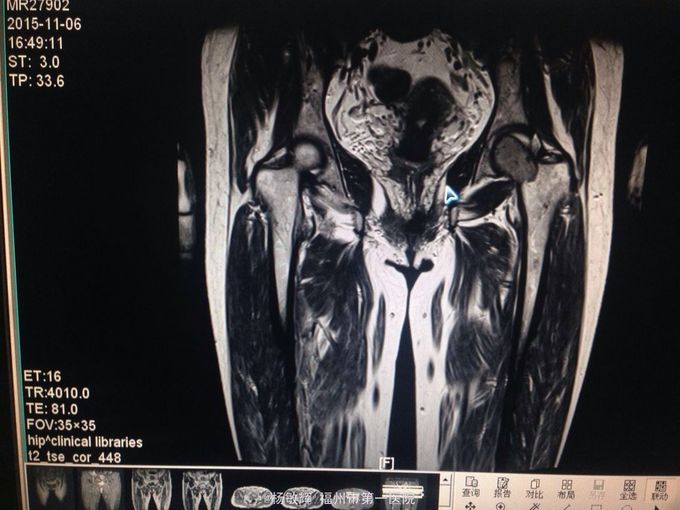

女性,48岁,以“左髋部疼痛伴活动受限2年”为主诉入院。缘于入院前2年无明显诱因出现左髋部疼痛不适,疼痛呈间歇刺痛,无向他处放射,伴左髋部活动受限,间歇性跛行,就诊当地医院查髋部X线提示:骨质破坏。MRI提示:左股骨头异常信号。当地医院诊断股骨头占位,未予以特殊处理,2周前疼痛加剧,就诊我院,查左髋部MRI提示:左髋部占位,骨巨细胞瘤可能性大。入院后于穿刺活检送病理,病理结果:左股骨头骨巨细胞瘤。拟:左股骨近段骨巨细胞瘤,收住院。

左股骨近段骨巨细胞瘤 入院后完善相关术前检查,未见明显手术禁忌症,行:左股骨近段占位切除+人工髋关节置换术